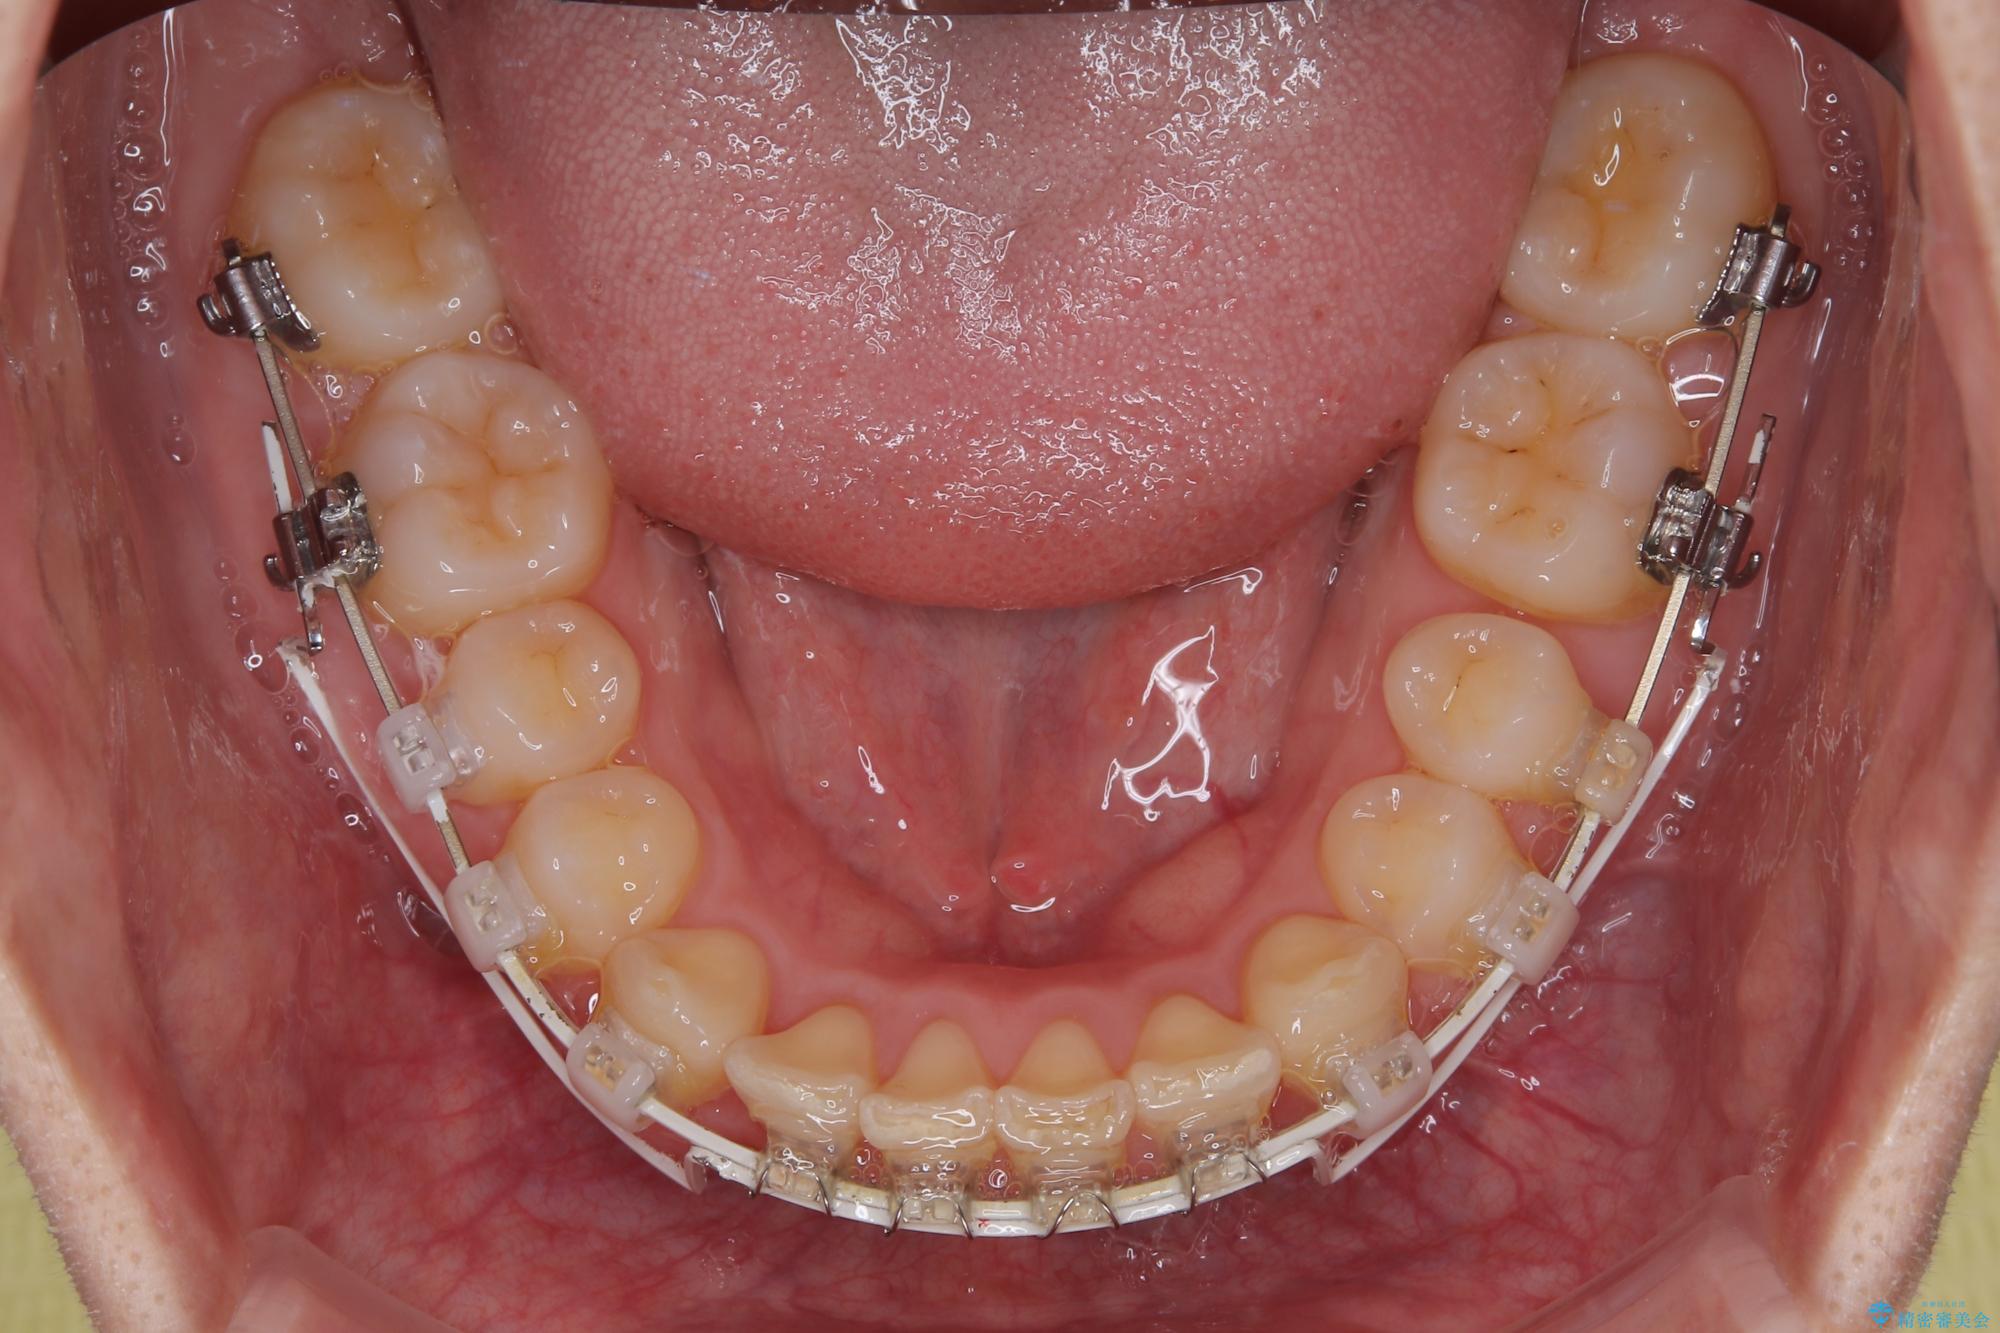

- 審美装置

下顎臼歯を起き上がらせるためにユーティリティーアーチを使用し、一気に深い咬み合わせを改善することができました。